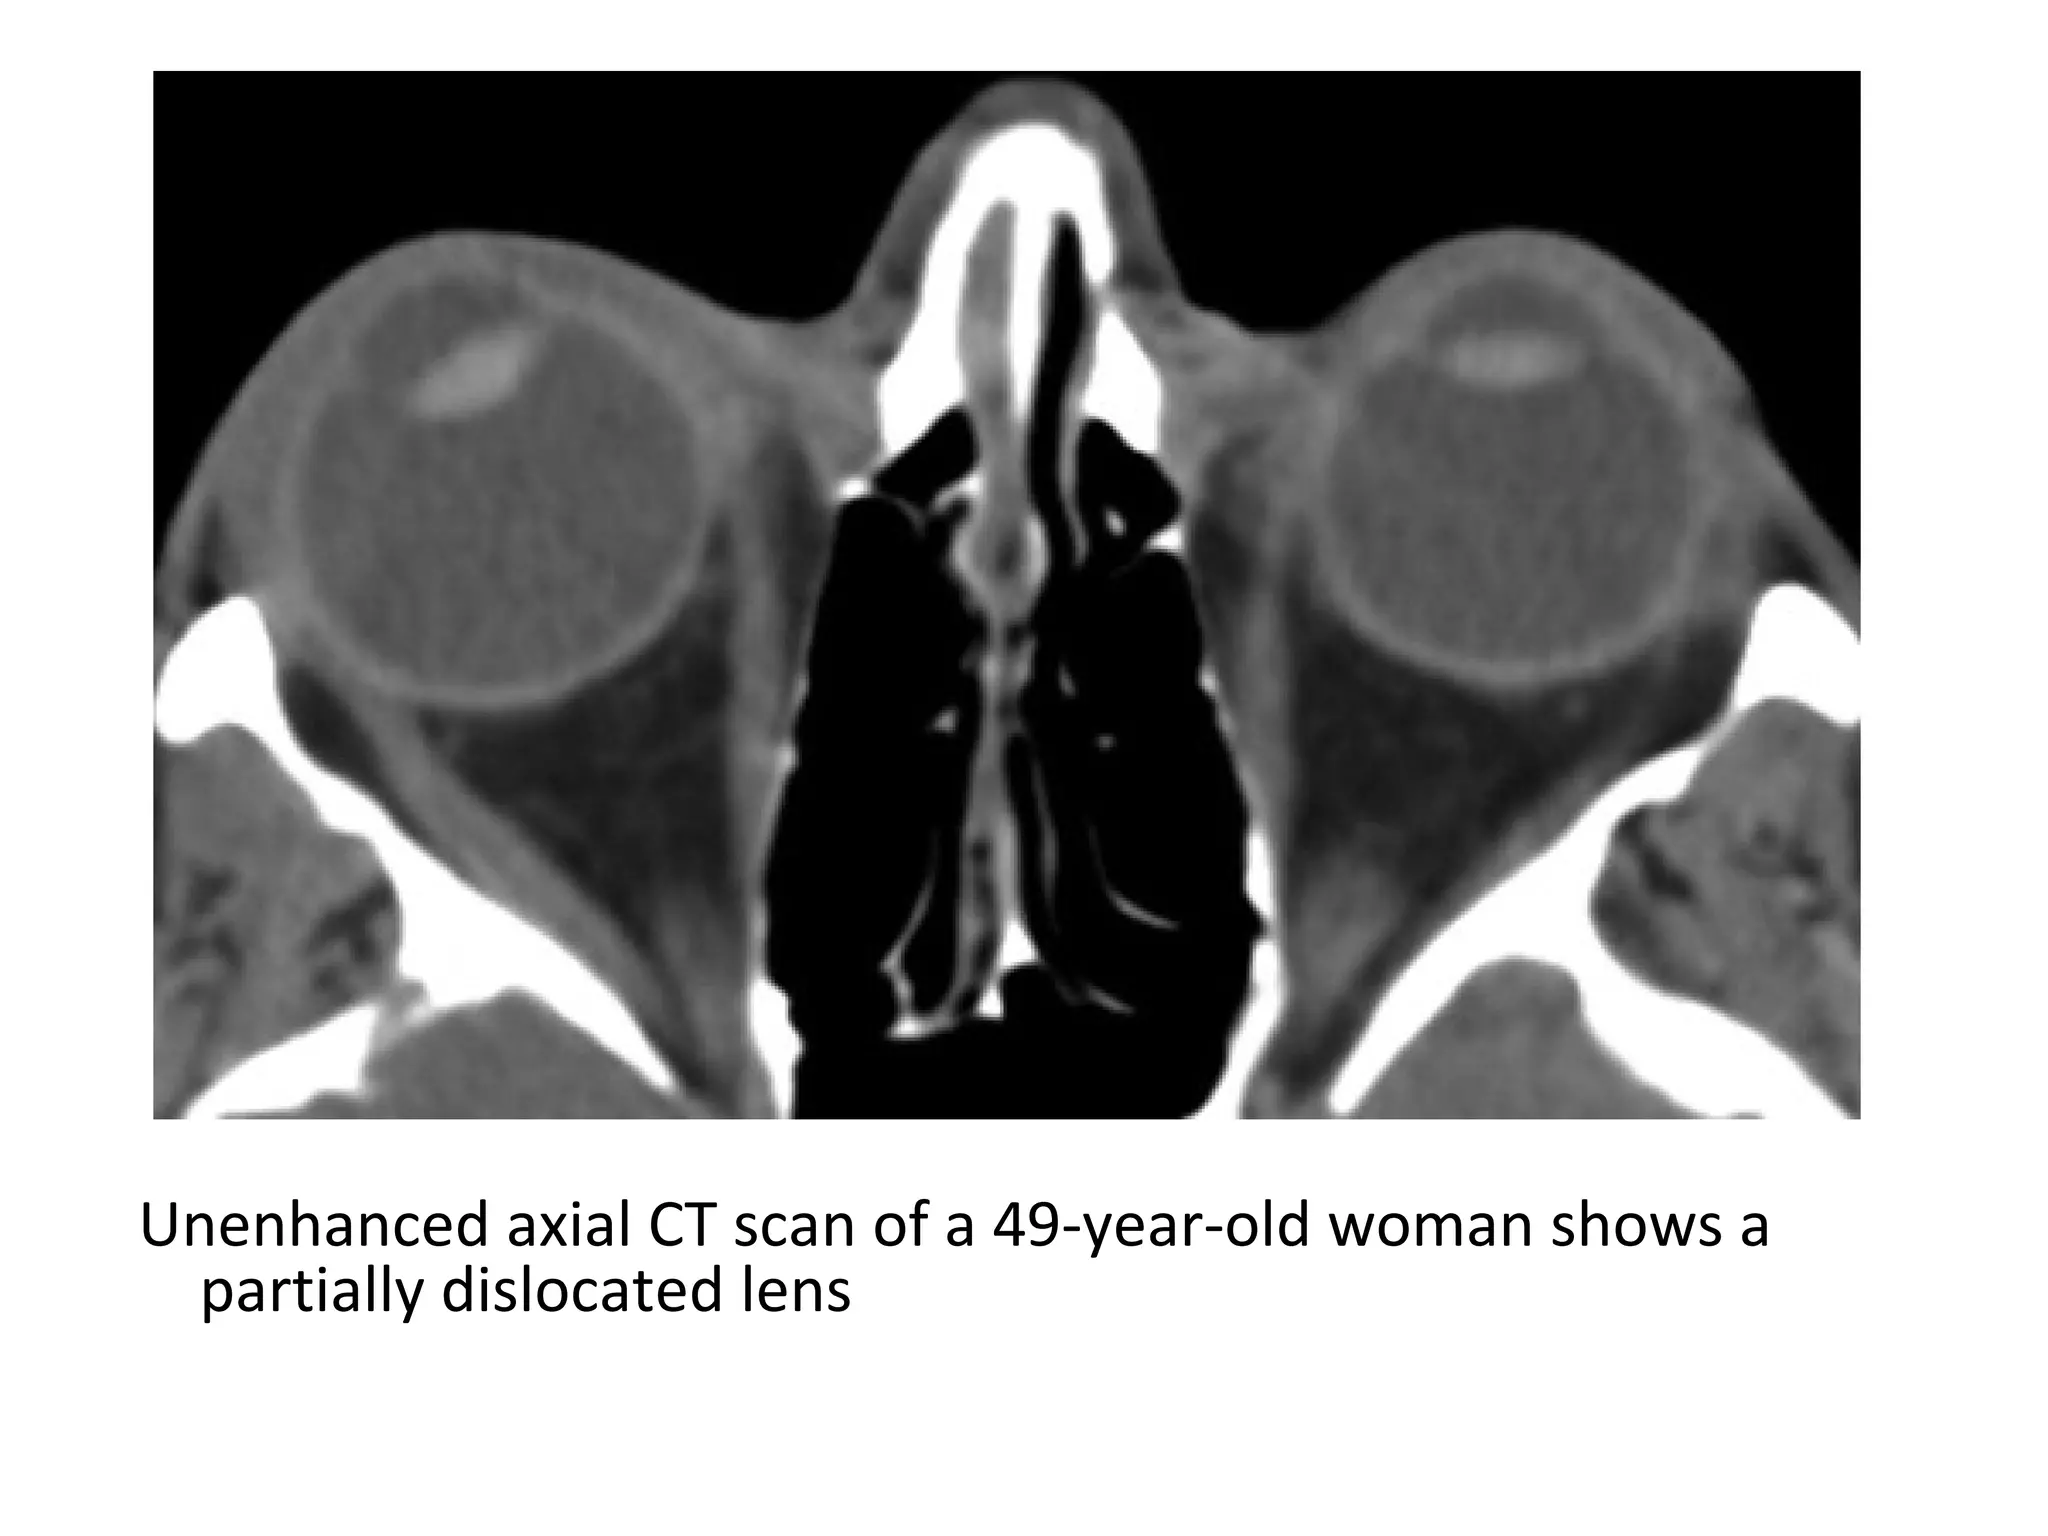

Unenhanced axial CT scan of a 49-year-old woman shows a

partially dislocated lens

2-Injuries to the Lens :

-Blunt trauma to the eye results in deformation of the

globe and typically displaces the cornea and anterior

sclera posteriorly

-Deformation of the globe causes the zonular

attachments that hold the lens in position to stretch

and potentially tear; tearing of the zonular

attachments may be either partial or complete

-After a complete disruption, the lens may dislocate

posteriorly or, less commonly, anteriorly

-Posterior dislocations are more common, in part

because the iris impedes anterior subluxation of the

lens

-After complete posterior subluxation, the lens usually

lies within the dependent portion of the vitreous

humor

-If there is only partial disruption of the zonular fibers,

the intact fibers retain one margin of the lens in its

normal position just behind the iris while the

remainder of the lens is angled posteriorly and

projects into the vitreous humor

-Trauma is the most common cause of lens dislocation;